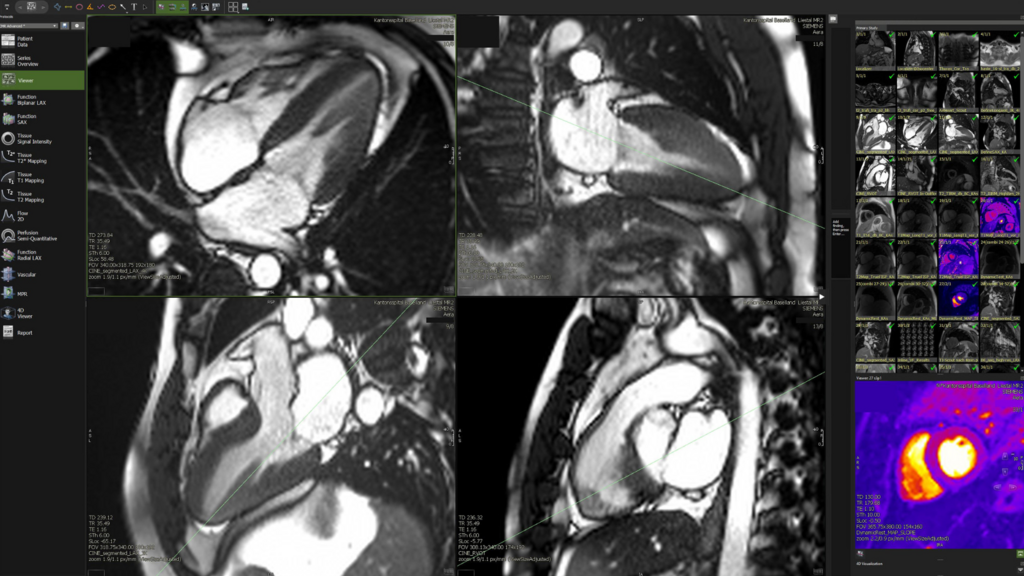

Das «European-Diploma in Cardiovascular Radiology» ist eine europäische Zertifizierung als Spezialist für Herz-Kreislauf-Bildgebung, welche die spezifische Kompetenz von Radiologen bestätigt, kardiovaskuläre CT- und MR-Untersuchungen auf hohem Niveau selbstständig durchzuführen, zu interpretieren und zu beurteilen.

Prof. Dr. Dr. Deniz Bilecen hat an der Universität Basel Biochemie studiert und doktoriert. Anschliessend hat er sich entschieden, ein Medizinstudium in Angriff zu nehmen und nach der Approbation ebenfalls zu doktorieren. Danach hat er seine Facharztausbildung in der Radiologie am Universitätsspital Basel absolviert. Er ist Titularprofessor an der Universität Basel im Fach Radiologie und derzeit am Kantonsspital Baselland (KSBL) am Standort Liestal für die kardiothorakale Bildgebung (Organe des Brustkorbs) zuständig.